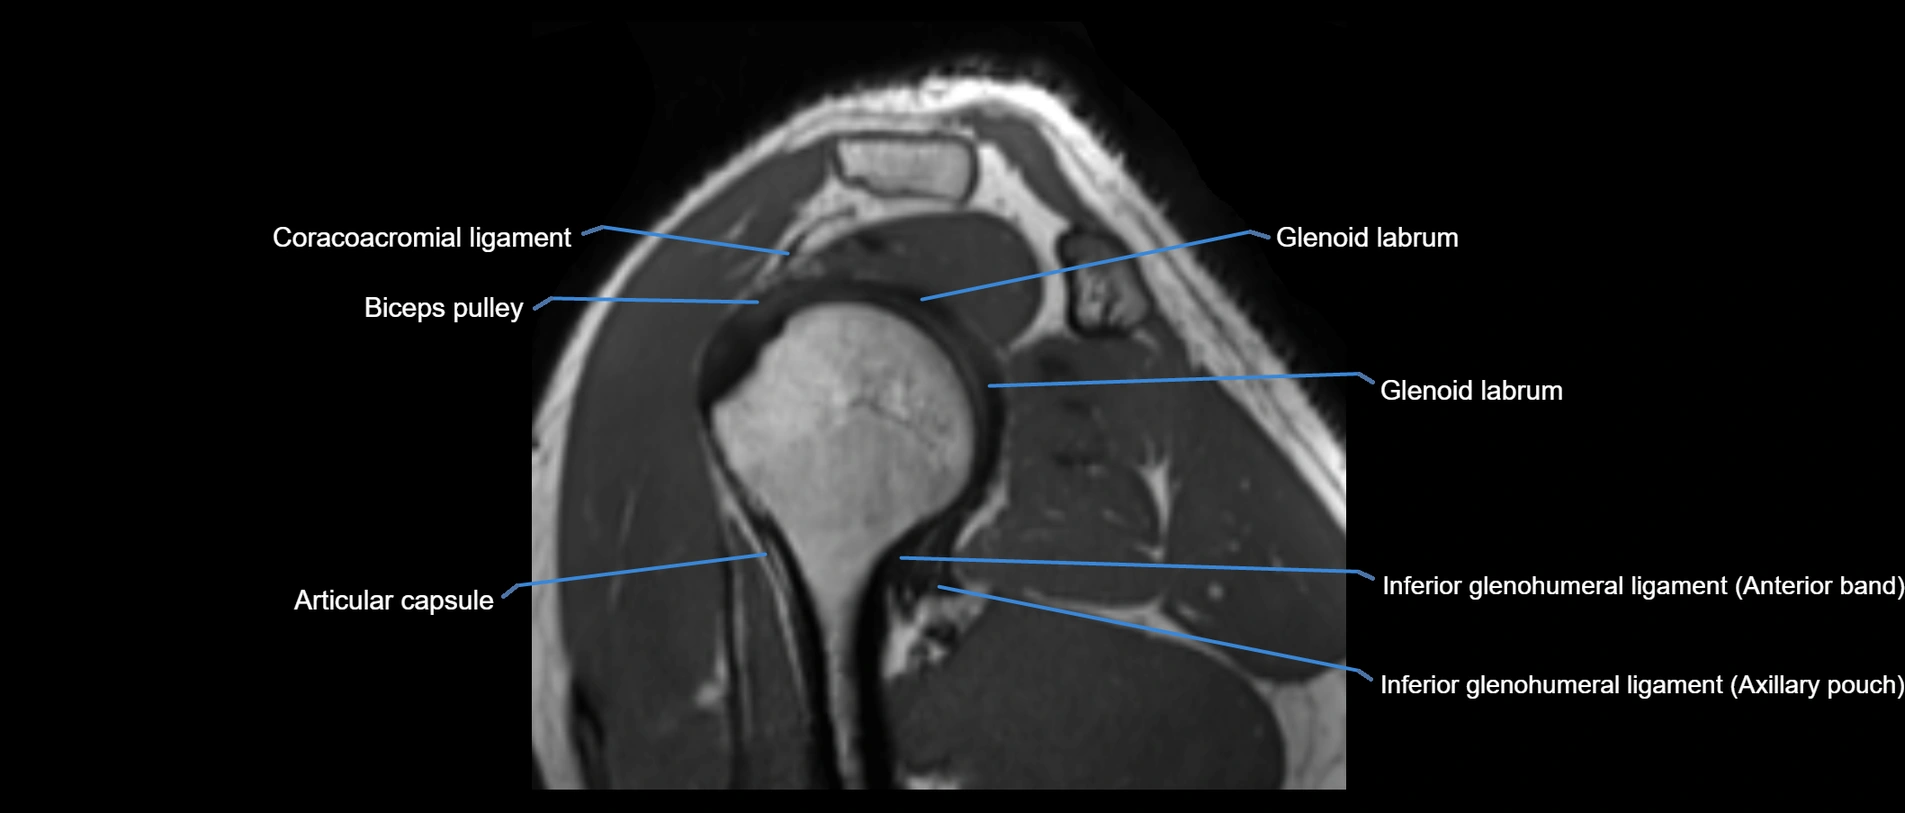

MRI images

image

MRI Appearance

• STIR:

• Normal ligament: Dark linear band.

• Injury or inflammation: Bright hyperintense signal in and around ligament fibers.

• Highlights periligamentous soft-tissue edema, especially in acute trauma.

• Proton Density Fat-Saturated (PD FS):

• Normal ligament: Low signal, uniform thickness.

• Partial tear or sprain: Bright signal or contour irregularity.

• Complete tear: Clear discontinuity with bright signal gap and joint effusion.

• Excellent for assessing joint capsule, coracoclavicular ligaments, and periarticular edema.